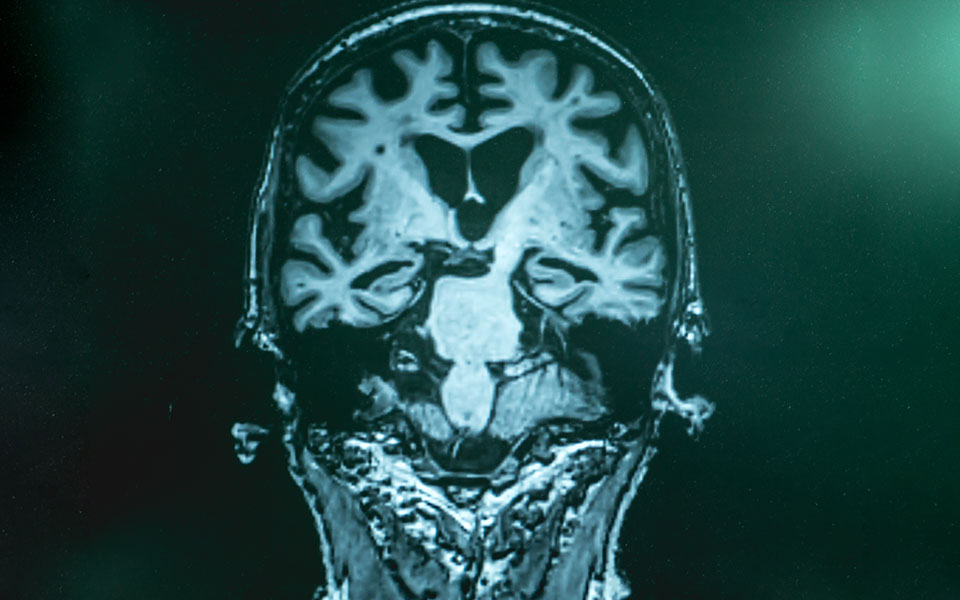

Διαθέτουμε, άραγε, το μέσο που θα βελτιώσει την οδυνηρή καθημερινότητα εκατομμυρίων πασχόντων από Aλτσχάιμερ ή, για μία ακόμη φορά, οι ελπίδες μας θα διαψευσθούν; Aυτό το καυτό ερώτημα γέννησε η έγκριση του σκευάσματος Aducanumab της Βiogen από τον αμερικανικό Οργανισμό Τροφίμων και Φαρμάκων (FDA), στις αρχές της εβδομάδας.